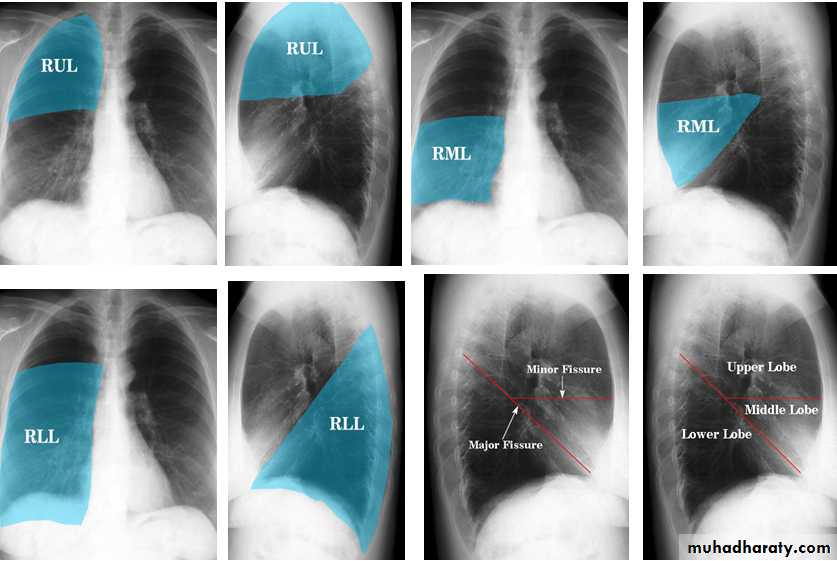

The left lung has two lobes and the right has three

Each lobe has its own pleural covering

The horizontal fissure (right) is often seen on a normal frontal view

The oblique fissures are often seen on a normal lateral view .

Lobes and fissures

This cut-out of a lateral chest x-ray shows the positions of the lobes of the right lung

On the left the oblique fissure is in a similar position but there is usually no horizontal fissure, and so there are only two lobes on the left.

Radiologic anatomy of the RT lung lobes

Radiologic anatomy of the LT lung lobes